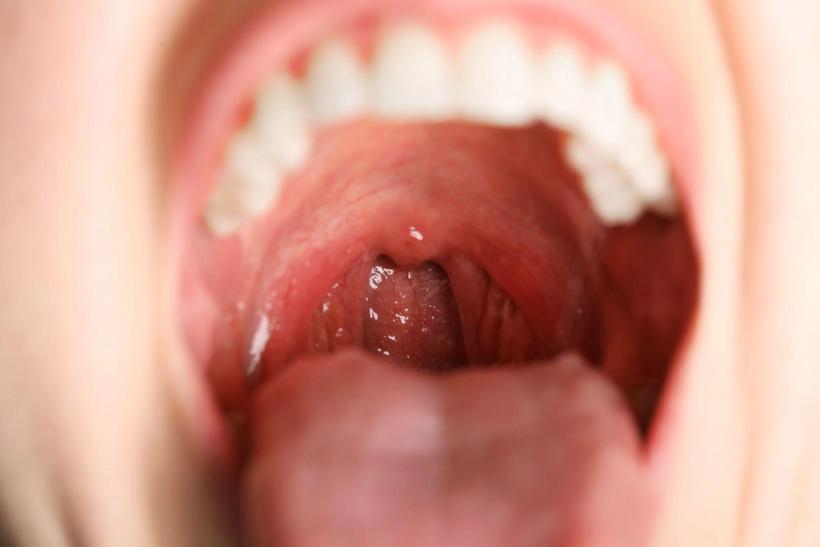

What does strep throat look like?

Strep throat often causes red, swollen tonsils with white patches or streaks of pus. You might also see small red spots on the roof of the mouth.

- Red, swollen tonsils with white patches or streaks of pus

- Tiny red spots on the roof of the mouth